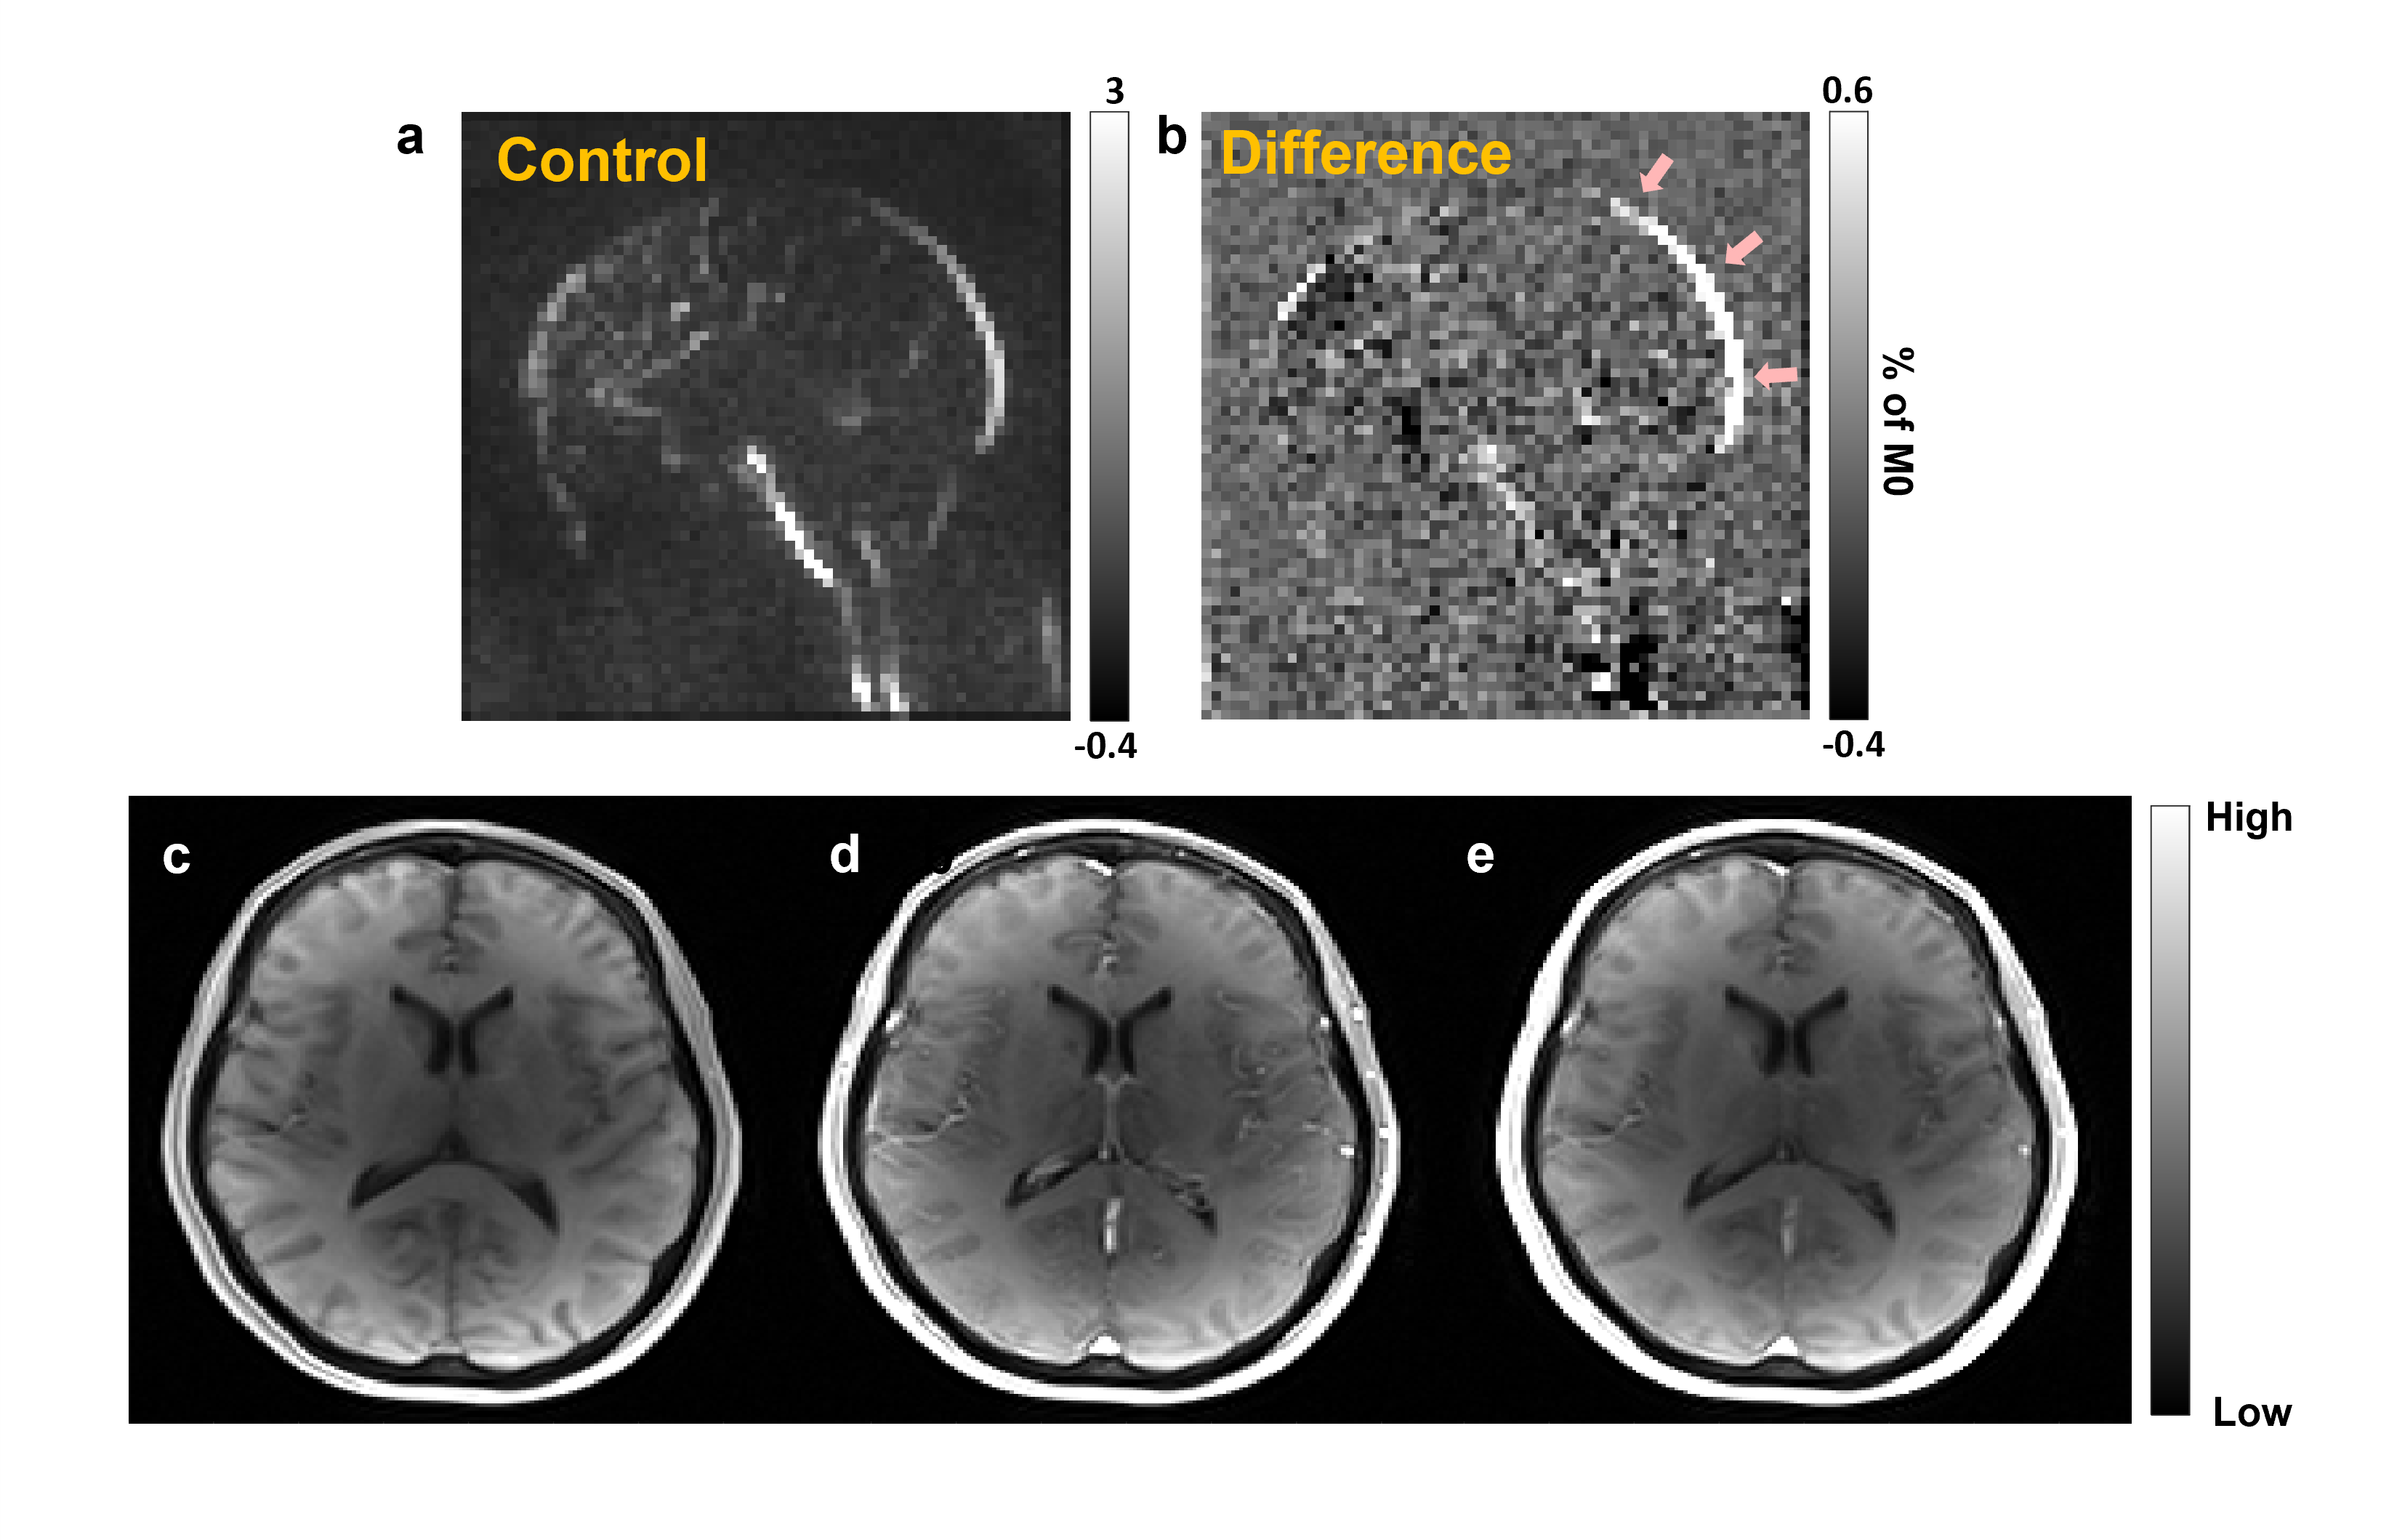

Figure-1 shows the WEPCAST control and difference images (figure-1(a),(b)) and DCE-MRI images at the baseline (c), first-pass peak (d) and final temporal point (e). Figure-2 shows the error bars of C(t) (red plot) and AIF (blue plot) measured across the cohort (figure-2 (a)) along with the box plot of estimated Ktrans values. eTofts model was able to fit all the mean curves with the estimated AIF from SSS with a mean good-ness of fit (R2) > 0.85. Even though relatively large variability in AIF (CoV = ~53%) introduced variabilities in Ktrans from DCE-MRI data, it didn’t affect the reliability of data fitting and computation. Ktrans computed from DCE-MRI and WEPCAST data were in good agreement as shown in figure-3 with correlation co-efficient 0.76 (p = 0.01). It could be noted that a linear regression model fits the data with good agreement. Since the sample size of the data presented in this study is relatively small, further optimization and validation of this study is required in much larger cohort before clinical translation.

Figure-1: (a), (b) show the control and difference images computed from WEPCAST data. Arrows in (b) highlights the regions where we computed the global Ktrans. (c)-(e) represent the DCE-MRI dunamic images acquired before contrast agent intake (c), peak of first-pass (d) and during final temporal point (e)